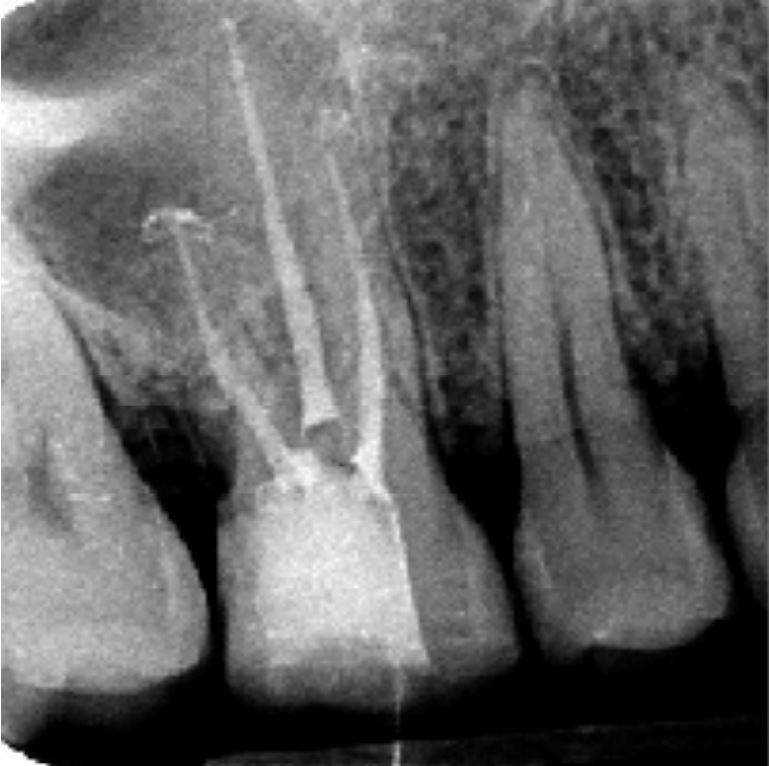

Obturation Gutta et Ciment Zinc Eugénol

Thermocompactage